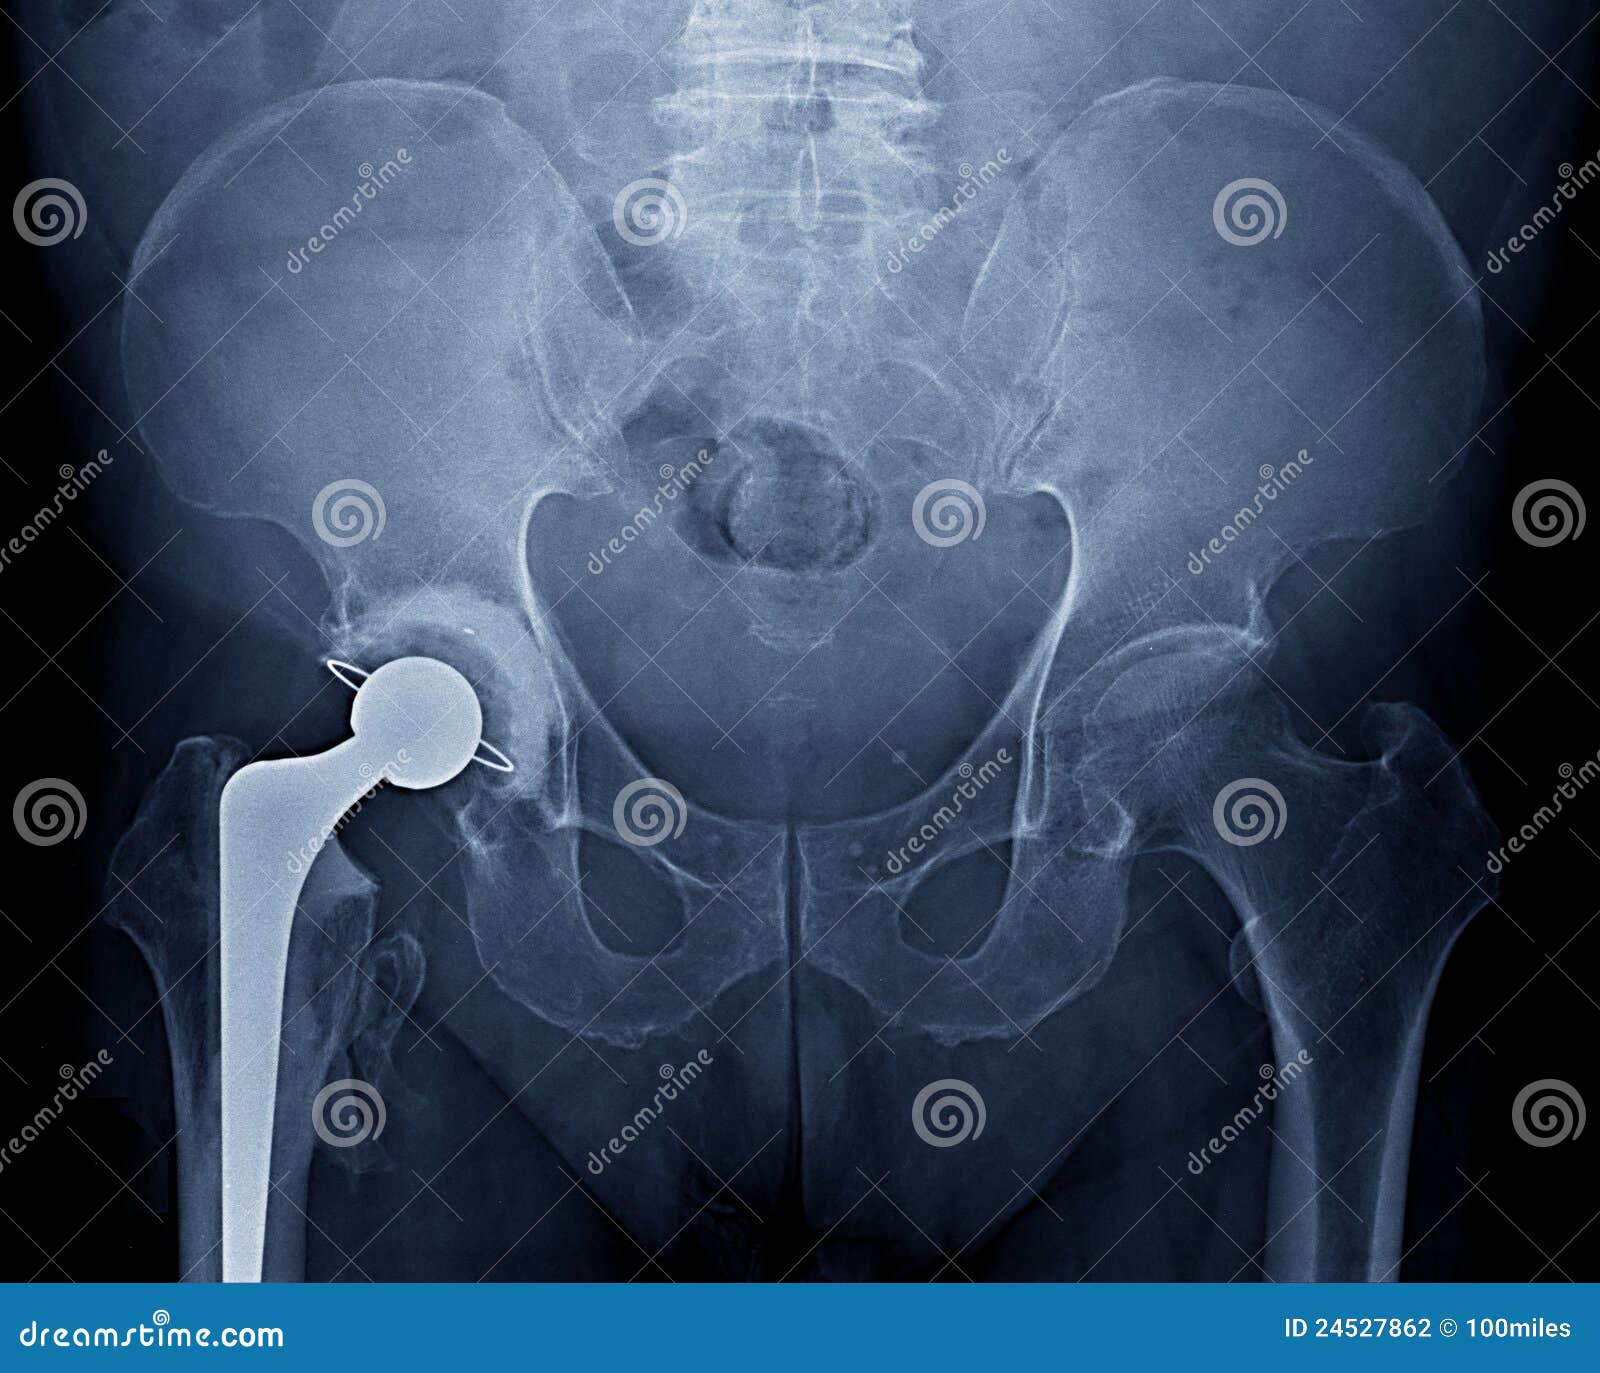

From www.dreamstime.com

Pelvic Xray Stock Photography Image 24527862 Hip Replacement Radiation Therapy in recent years, the number of hip replacement patients receiving radiation therapy has steadily increased. radiotherapy with medium dose (20 gy ≤ bed ≤ 24 gy) after tha is an effective dose for preventing ho. alongside advances in total hip arthroplasty (tha), innovations in the treatment of cancer have led to an. the goals of future. Hip Replacement Radiation Therapy.